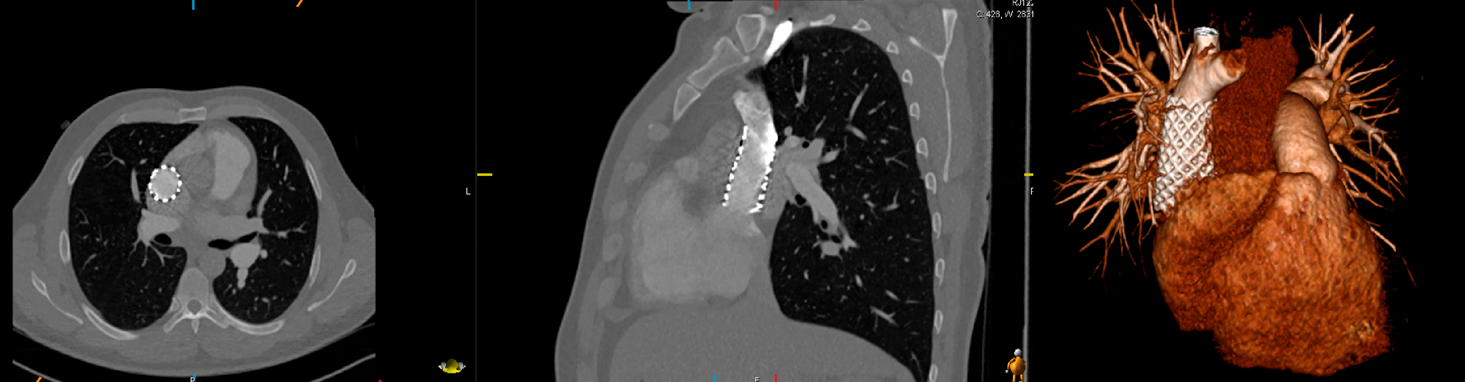

【ABL/カテ検査】 検査・治療|循環器内科|大阪市立総合医療センター循環器センターの詳細情報

検査・治療|循環器内科|大阪市立総合医療センター循環器センター。神戸アドベンチスト病院 | カテーテル検査・治療。Argyle™ Fukuroi CV カテーテル セルジンガー キット。あんず⚠︎2冊とも裁断済みです⚠︎これから始める カテーテルアブレーションこれから始める 心臓カテーテル検査発送は7/11となります。ACHDのカテーテル治療:現在まで,そして未来へ。よろしくお願い致します。病気がみえる vol.3 糖尿病・代謝・内分泌。